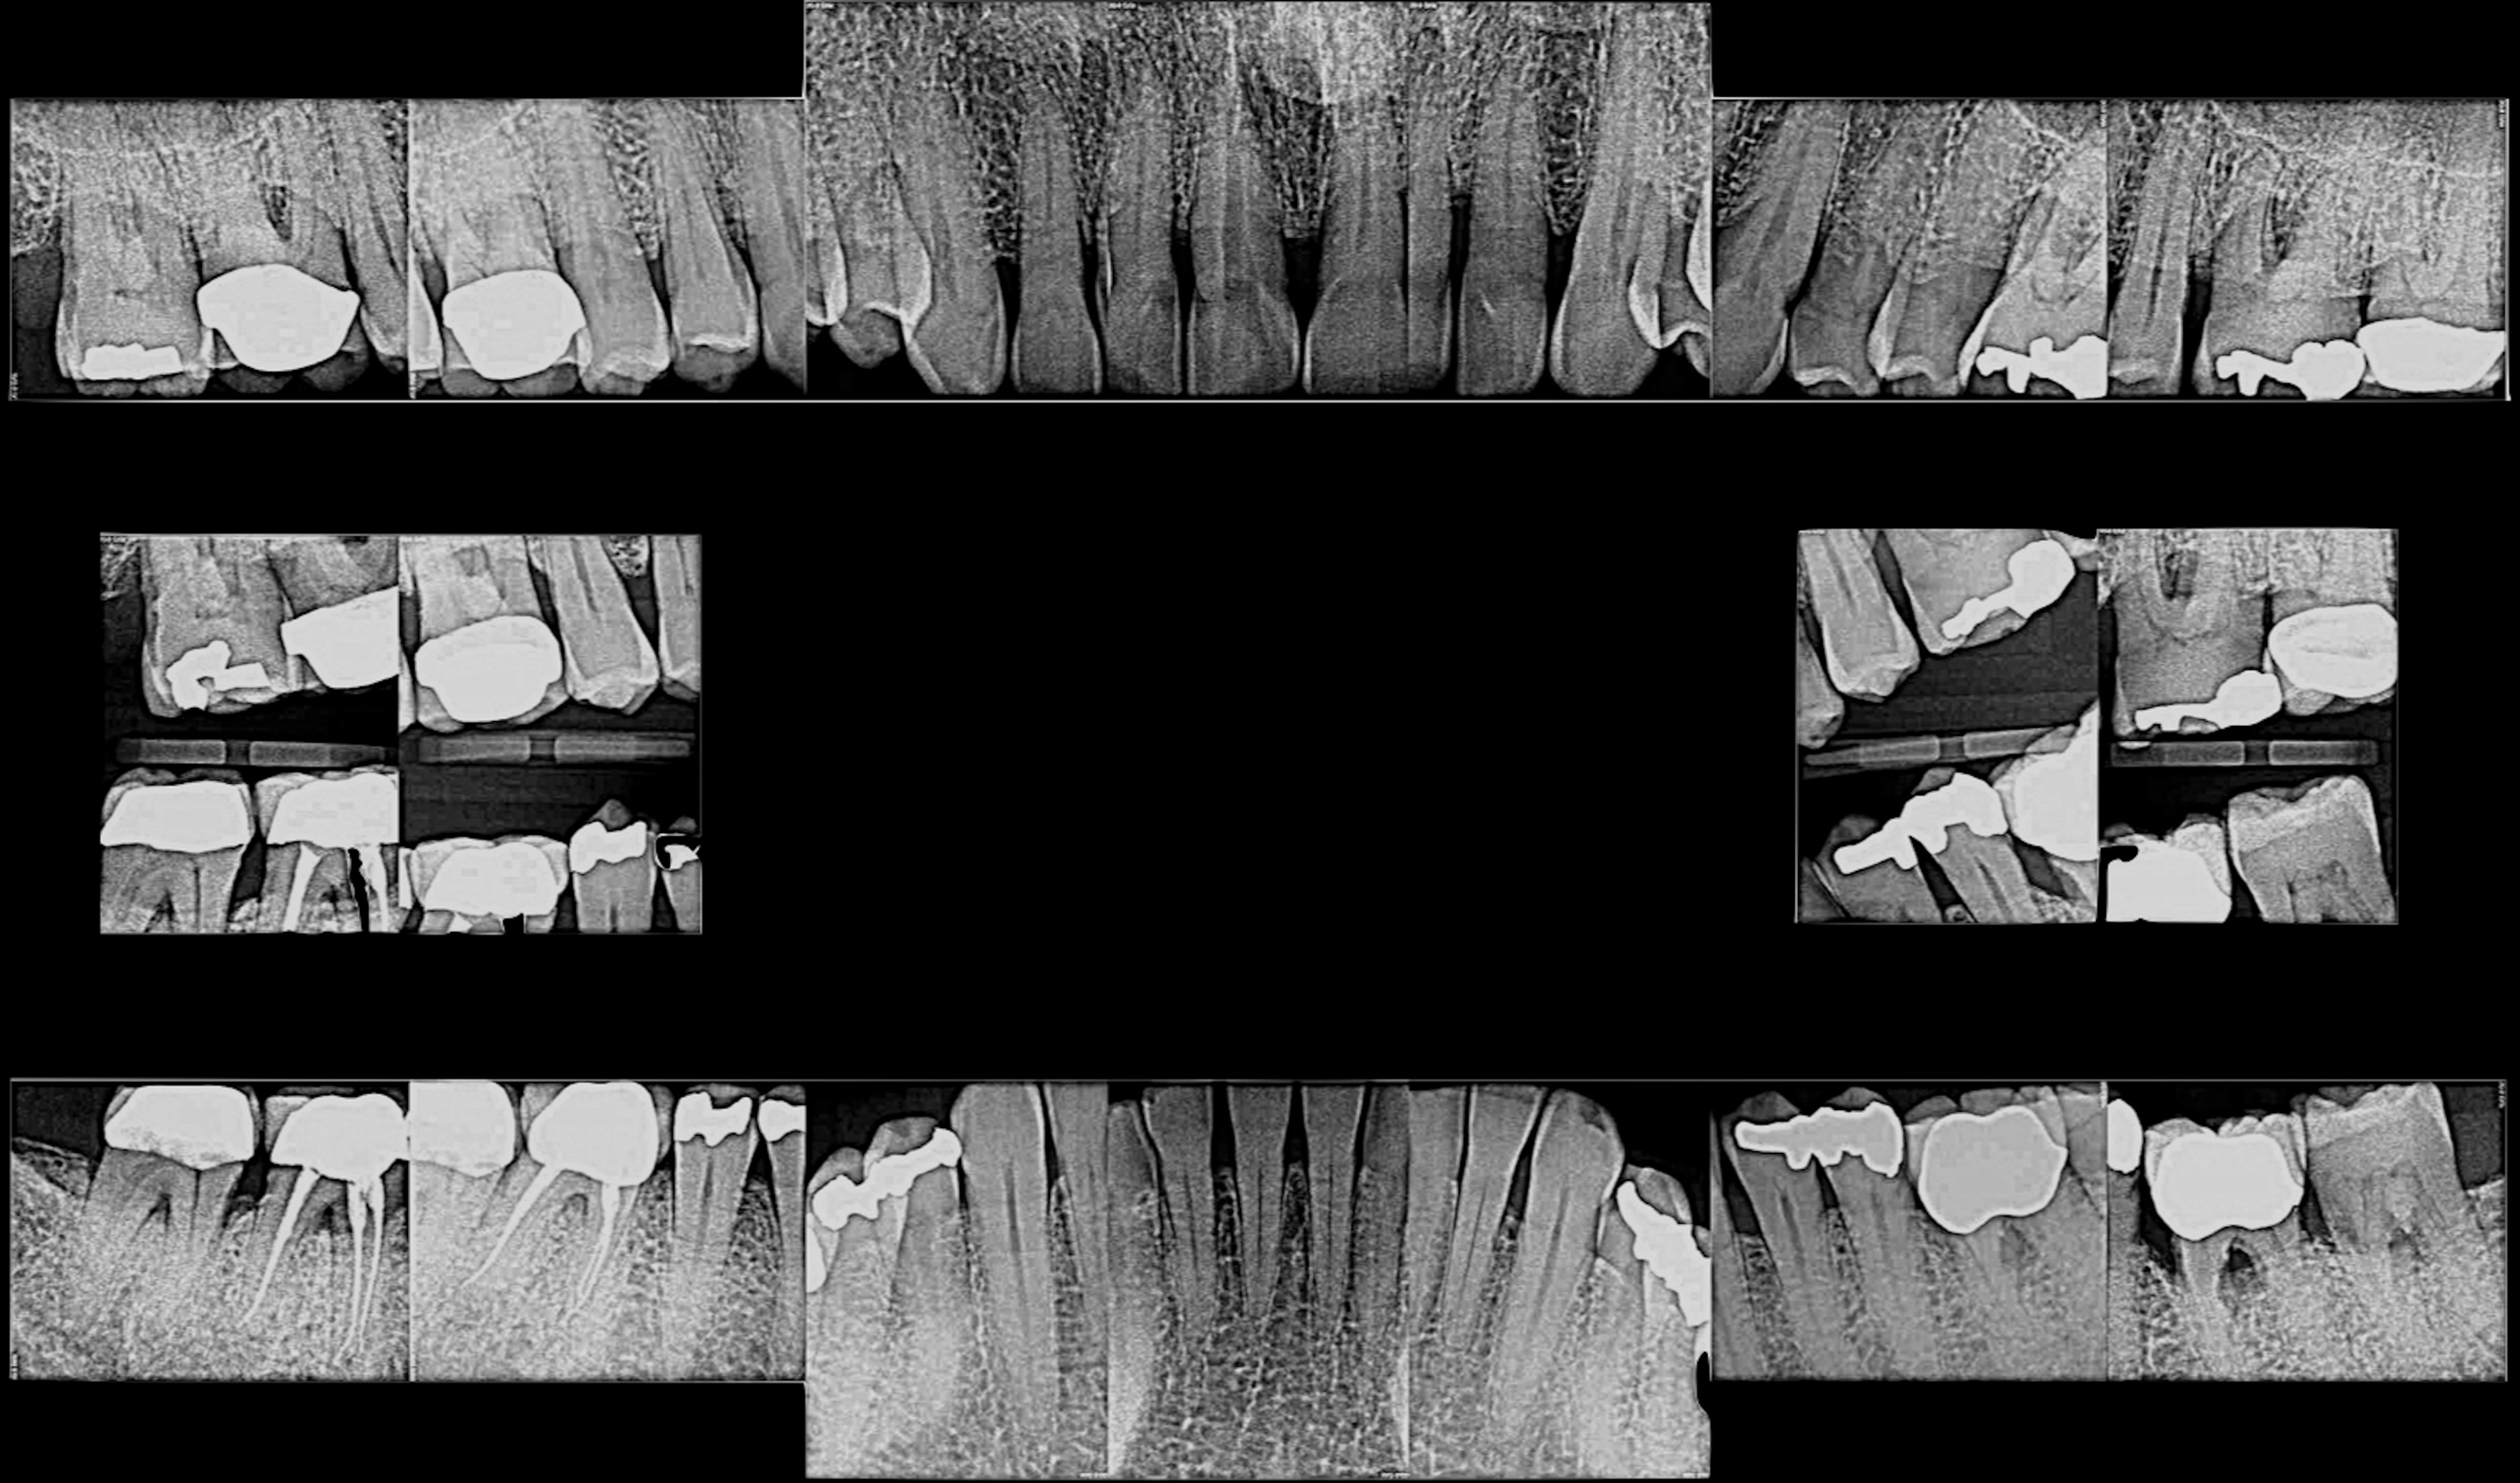

Periodontal examination revealed generalized BOP and PDs up to 9 mm in the maxillary and mandibular molars with multiple furcations in each molar (Figure 2 through Figure 7). He presented with class I mobility in many posterior teeth and class II mobility in teeth Nos. 3 and 9 (maxillary right first molar and maxillary left central incisor, respectively). The periodontist decided to score tooth No. 3 for the PRS, as this was the most periodontally involved molar that was planned to be treated and maintained (Figure 2 and Figure 8). This tooth (maxillary right first molar = score 1) presented with probing depths of 7 mm (score 1); three total furcation invasions (score 3) (mesial [degree II furcation], buccal [degree I furcation], and distal [degree II furcation]); and a class II mobility (score 2). The total PRS for tooth No. 3 was 8, representing a "guarded" prognosis. Based on this score, the likelihood of not losing any teeth to periodontal disease for 15 years was 81%, and for 30 years the likelihood was just 56% (Figure 9).7

Fig 2. Pretreatment views: right lateral (Fig 2), frontal (Fig 3), and left lateral (Fig 4). Note: The maxillary right first molar (tooth No. 3) (Fig 2) would be identified as the most periodontally involved molar that was planned to be maintained.

Figure 2

Fig 7. Pretreatment periapical radiographs.

Figure 7